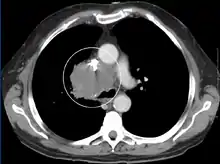

The main techniques of diagnosing SVCS are with chest X-rays (CXR), CT scans, transbronchial needle aspiration at bronchoscopy and mediastinoscopy.[6] CXRs often provide the ability to show mediastinal widening and may show the presenting primary cause of SVCS.[6] However, 16% of people with SVC syndrome have a normal chest X-ray. CT scans should be contrast enhanced and be taken on the neck, chest, lower abdomen, and pelvis.[6] They may also show the underlying cause and the extent to which the disease has progressed.[6]